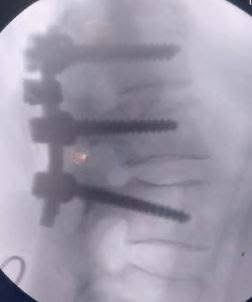

استمر الفريق في تحقيق إنجازاته، حيث أجرى جراحة دقيقة لمريض يعاني من خذل نصفي بسبب ورم بالفقرات الصدرية، مما أدى إلى تحسن حالته فورًا. كما نجح في استئصال ورم بالمخ لسيدة تبلغ من العمر 51 عامًا باستخدام الميكروسكوب الجراحي.